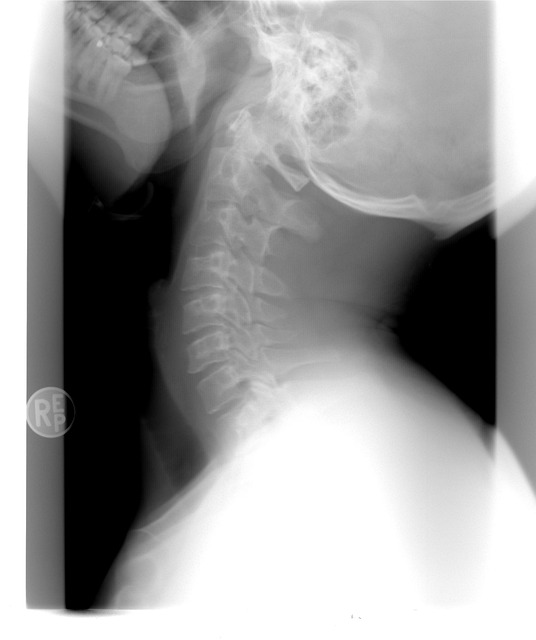

영상 검사 필요성

이학적 검사로만은 정확한 진단이 어려울 수 있기 때문에, 영상 검사가 필수적입니다. 이 단계의 검사는 다음과 같이 이루어집니다:

- 엑스레이 (X-ray): 뼈의 형태 변화나 관절 간격 감소, 골극 형성을 확인할 수 있습니다. 관절염이 진행될수록 관절 간격이 좁아지며, 이런 소견은 조기 진단에 매우 중요합니다.

- 자기공명영상 (MRI): 연골과 인대, 근육 등의 연부 조직 상태를 더욱 자세히 파악할 수 있는 검사입니다. 특히 초기 관절염 진단에 유용합니다.

- 초음파 검사 (Ultrasound): 활액막의 염증 상태나 관절 내 물의 양을 실시간으로 확인할 수 있습니다.

이러한 영상 검사를 통해 무릎의 상태를 정확히 평가함으로써 적절한 관리 및 치료 계획을 세울 수 있습니다

.

- X-ray 소견: 정상 소견이거나 관절 간격이 약간 좁아진 것을 확인할 수 있습니다.

- X-ray 소견: 관절 간격의 좁아짐과 뼈의 가장자리에 골극이 형성되기 시작합니다.

- X-ray 소견: 관절 간격이 현저하게 좁아지고, 골극의 크기가 커지며 뼈의 변형이 시작됩니다.

- X-ray 소견: 관절 간격이 완전히 사라지고, 뼈의 변형이 심하게 발생합니다.

이처럼 각 단계별로 관절염의 증상과 X-ray 소견이 다르게 나타나며, 적절한 관리와 조기 진단이 중요합니다. 여러분도 증상이 느껴진다면 주저하지 말고 전문의와 상담해보시길 바랍니다.